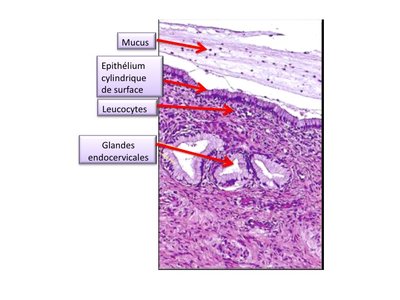

Photos ronéo Histo UE10 27/04

Voilà les photos en couleur :D Bon courage à tous pour ces prochains jours !!